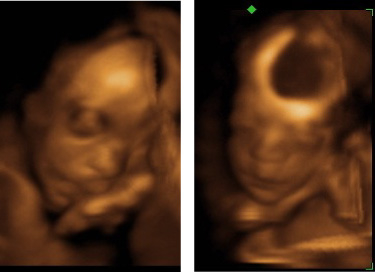

And what do you think—does he look like James or not? The first two pics are #3, and the last two are James a week younger:

Yes, they sure do look like brothers.

Hopefully #3 (would you hurry up and reveal, I’m too stupid to finish the puzzle!) has James’ beautiful expressive eyes and eyelashes that any woman would be jealous of!

Wow, #3 is chubby! James had more of mom’s face but baby #3 looks more like dad! He’s got a little button nose! He’s going to be absolutely beautiful ^_^; Congratulations!!!

my first thought was that #3 doesn’t look like James, but after seeing J’s ultrasound, I’m thinking their nose is alike.

They’re both adorable. They do look alike but it looks like #3 has a super cute little nose.

I definitely see a resemblance to James. Not so much comparing them in the ultrasounds, but the second ultrasound of Number Three, where you can see his face straight-on, he looks like several of the pictures that were posted of James. 🙂

WOW! I love the picture of #3’s profile. What a cute little nose he has! And I agree, you can definitely tell that he and James are brothers. I’m so happy for you three. Can’t wait till little Jonathan comes into the world!